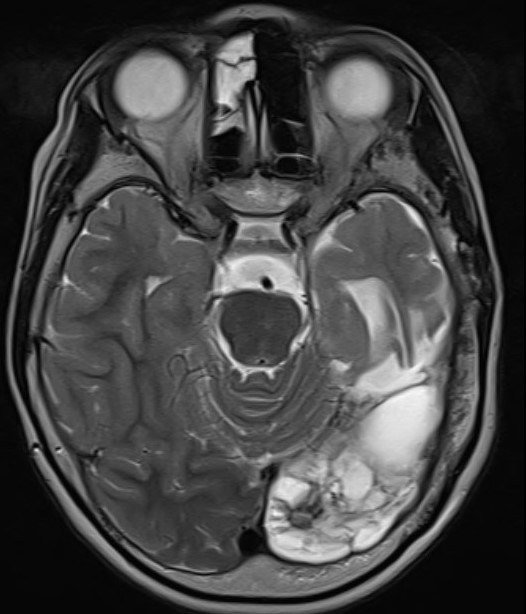

The following images accompany comments at the foot of this post.